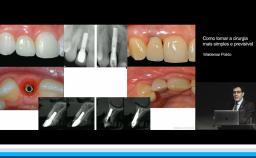

Surgical Planning and Procedures

Técnicas de aumento de tecido queratinizado ao redor de implantes

A apresentadora discute a importância dos tecidos moles e sua relação com saúde ou doença periimplantar. Discute-se os diferentes tipos de defeitos e técnicas cirúrgicas adequadas para aumento da quantidade de mucosa ceratinizada, visando melhor estabilidade tecidual ao longo dos anos. Por fim é apresentado o uso de um biomaterial para substituir tecido conjuntivo visando aumento de mucosa ceratinizada.